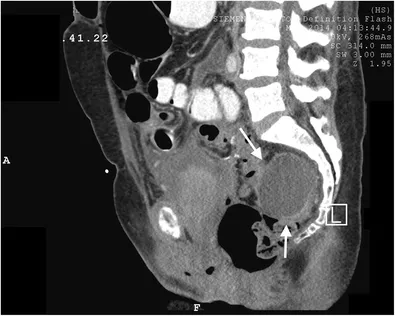

- Hemorrhage: Assess vitals, CBC. Pelvic US for hematoma; CT-A for active extravasation.

- Ureter: ↑Cr, flank pain. Dx: CT urogram, retrograde pyelogram.

- Bladder: Gross hematuria. Dx: Retrograde cystogram.

⭐ Ureteral injury often presents subtly 5-10 days post-op with flank pain, fever, or watery vaginal discharge (urinoma), not immediate anuria.